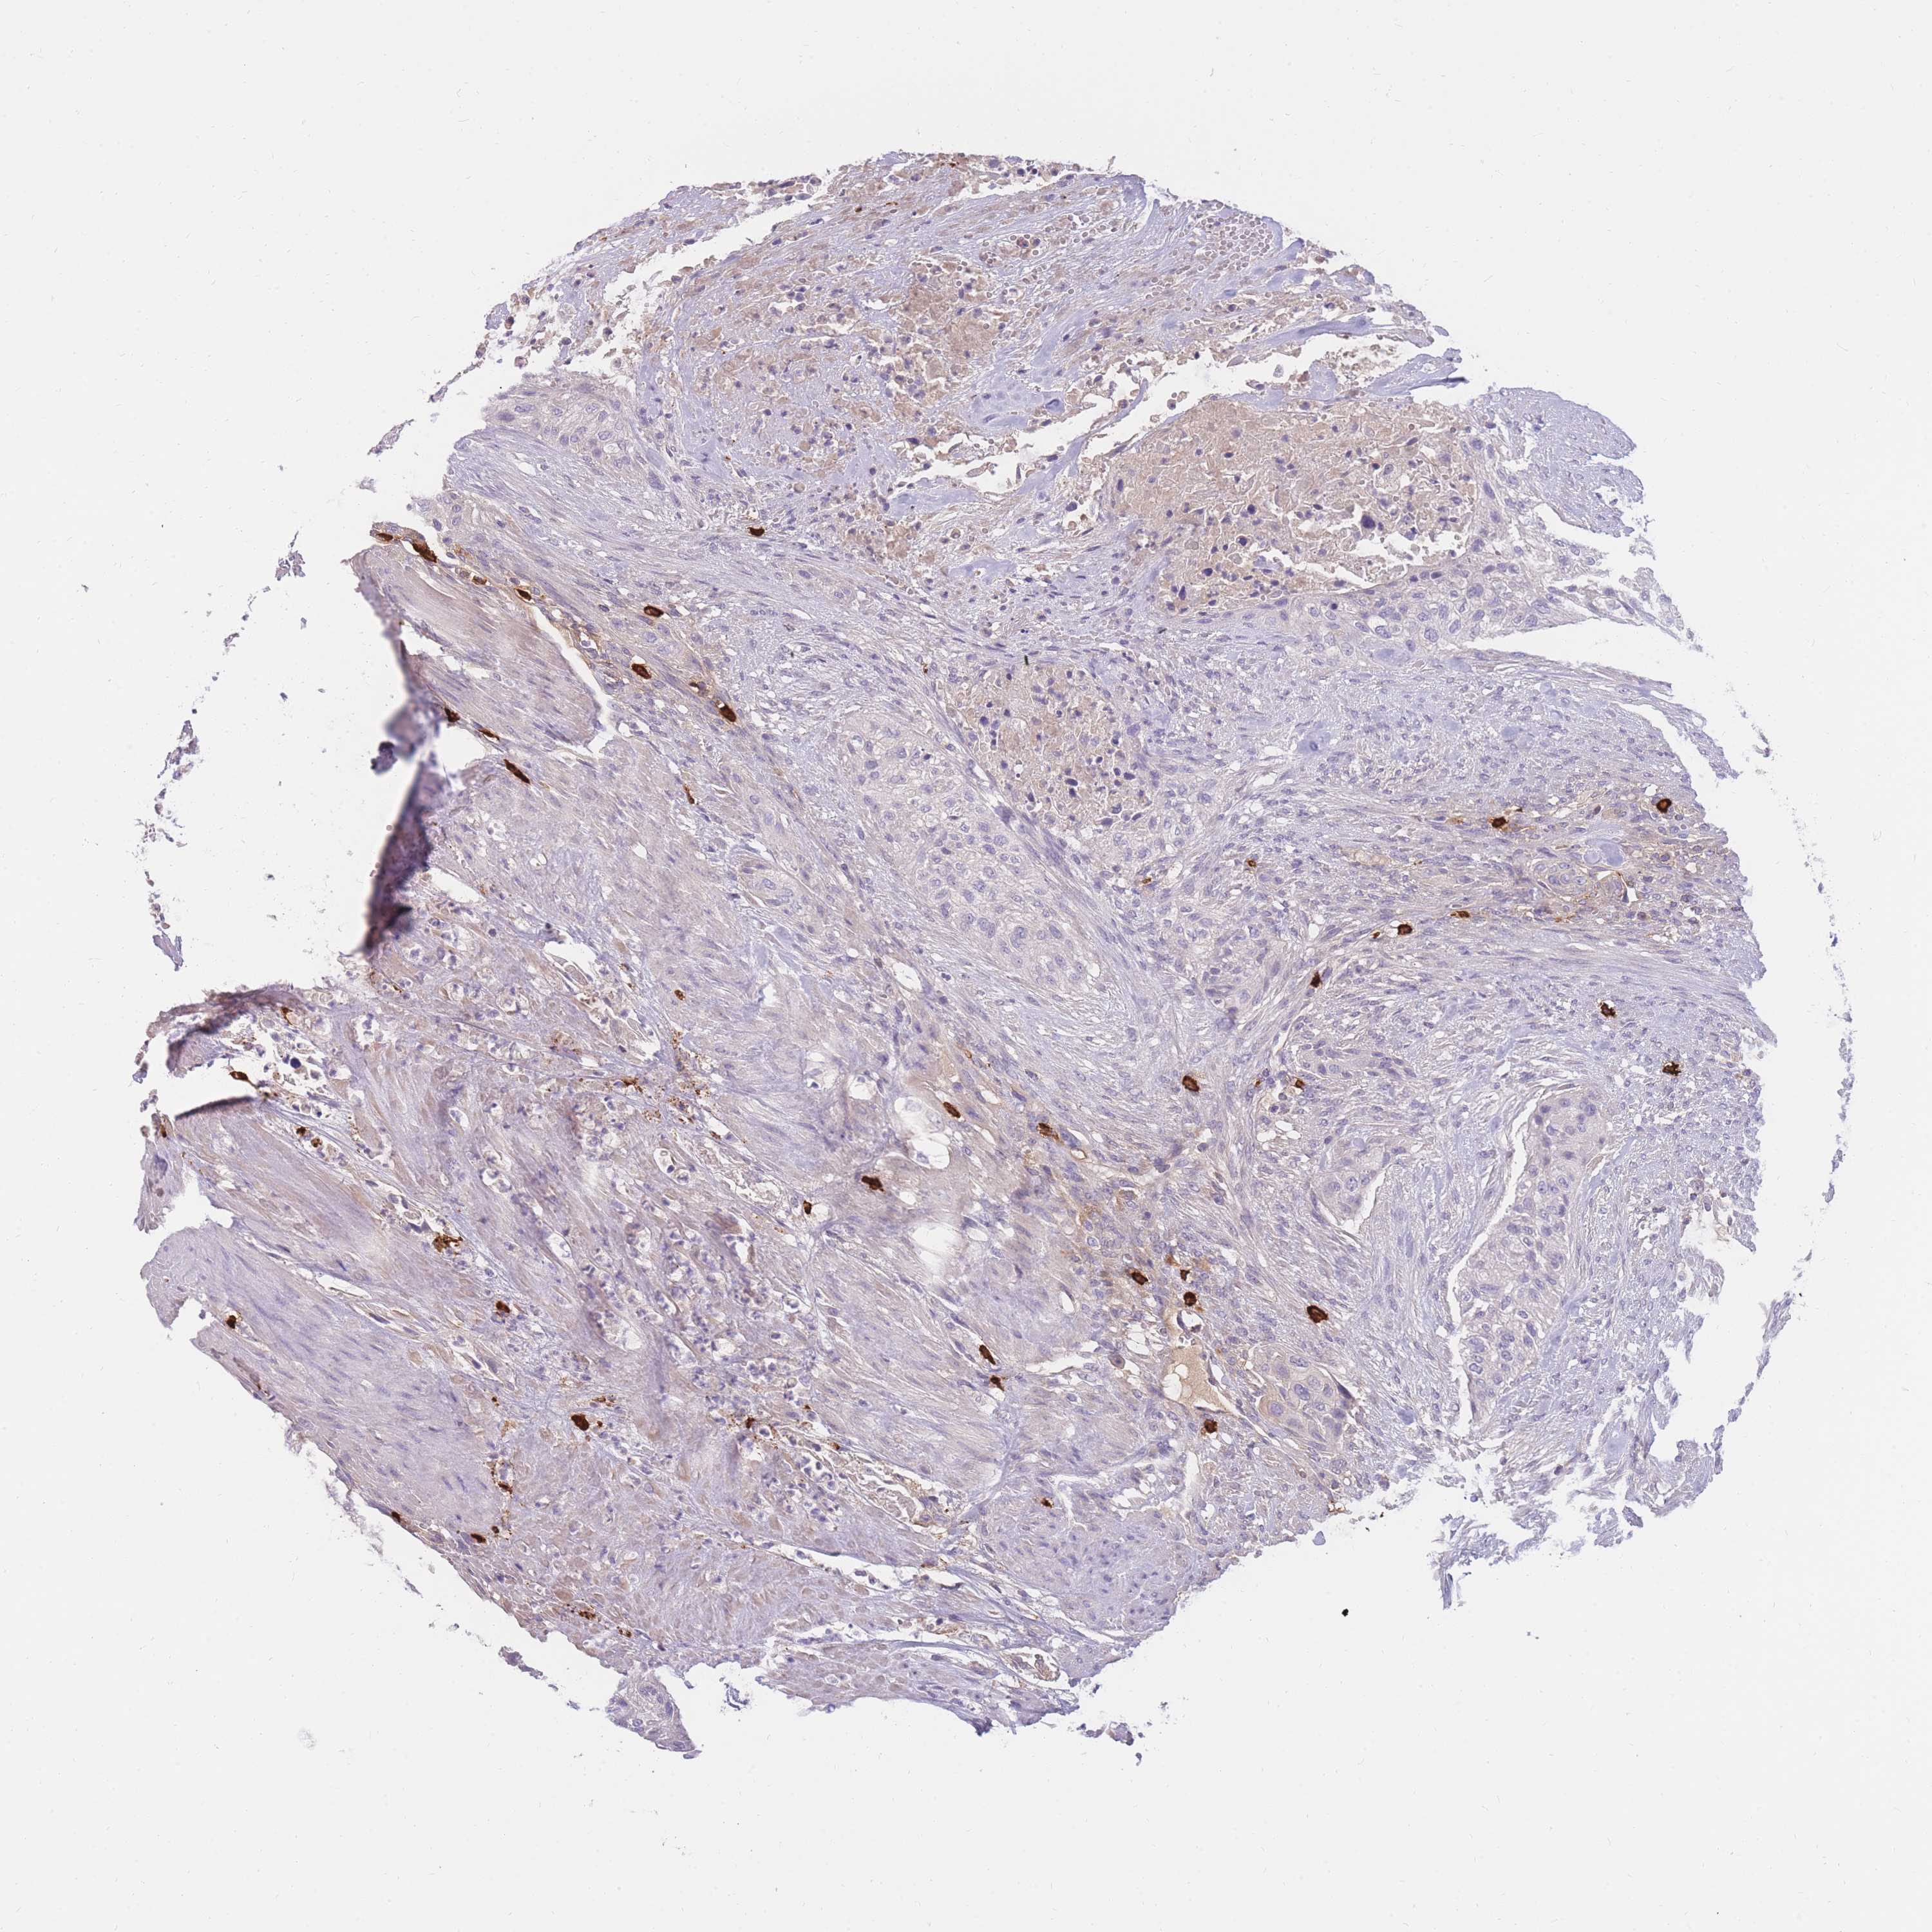

UROTHELIAL CANCER - Protein expressioni

A mouse-over function shows sample information and annotation data. Click on an image to view it in a full screen mode. Samples can be filtered based on level of antibody staining by selecting one or several of the following categories: high, medium, low and not detected. The assay and annotation is described here.

Note that samples used for immunohistochemistry by the Human Protein Atlas do not correspond to samples in the TCGA dataset.

Antibody stainingi

Antibody staining in the annotated cell types in the current human tissue is reported as not detected, low, medium, or high, based on conventional immunohistochemistry profiling in selected tissues. This score is based on the combination of the staining intensity and fraction of stained cells.

Each image is clickable and will lead to virtual microscopy that enables deeper exploration of all samples and also displays staining intensity scores, fraction scores and subcellular localization as well as patient and tissue information for each sample.

Antibody HPA040182

Antibody HPA049554

Antibody CAB002215

Antibody CAB032871

Staining

High

Medium

Low

Not detected

Intensity

Strong

Moderate

Weak

Negative

Quantity

>75%

75%-25%

<25%

None

Location

Nuclear

Cytoplasmic/membranous

Cytoplasmic/membranous,nuclear

Urothelial carcinoma, High grade

Urothelial carcinoma, NOS

Urothelial carcinoma, Low grade

Adenocarcinoma, NOS